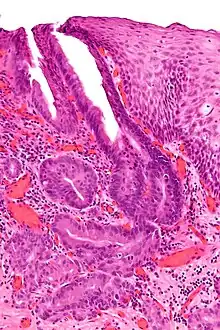

Oesophagogastric junctional adenocarcinoma

Oesophagogastric junctional adenocarcinoma (OGJ adenocarcinoma) is a cancer of the lower part of the oesophagus with a rising incidence in Western countries.[1] This disease is often linked to Barrett's oesophagus.

The diagnostic workup for OGJ adenocarcinoma usually involves performing an endoscopy with endoscopic biopsy of suspicious looking tissue. Accurate staging of tumor extent and involvement of surrounding tissue or distant metastases is critical to establishing a prognosis, and is usually guided by endoscopic ultrasound, computed tomography scans, and/or positron emission tomography scans to establish the extent of disease. Additionally, genetic analysis of the tumor may yield mutations that may be clinically significant, as described below.